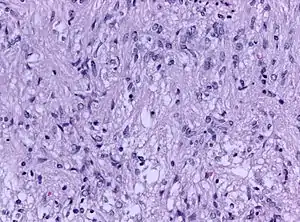

| Biopsy specimen of a pituicytoma of the posterior pituitary gland (H&E stain, x200 magnification) | |